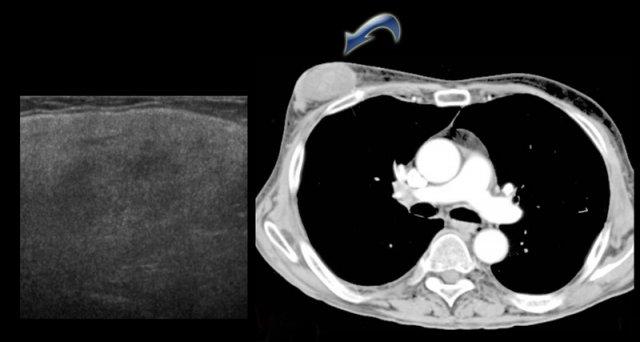

Bên trái là gynecomastia một bên.

Đây là phát hiện tình cờ trên CT được thực hiện vì một lý do khác.

Theo định nghĩa, gynecomastia là mô dưới quầng vú có kích thước từ 2 cm trở lên ở nam giới không béo phì.

Đây là một phát hiện ‘bình thường’ thường gặp, được ghi nhận ở 55% nam giới khi khám nghiệm tử thi.

Đỉnh tần suất mắc bệnh là ở độ tuổi 60 – 69.

Tình trạng này có ý nghĩa lâm sàng khi xuất hiện mới hoặc có triệu chứng.